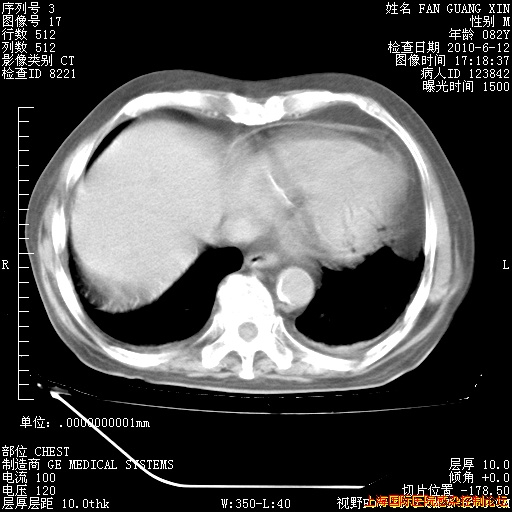

6月12日纵膈窗

回复

整整相隔30天的肺部CT好像有所好转啊。甲强龙减量第3天,需要观察体温。

海管,自昨日你和我通完话后,不知您岳父消化道症状有无缓解?体温怎样?阅读7.12日胸部ct,个人认为目前激素治疗是有效的,甲强龙减量是适宜的。因在抗痨治疗,需密切观察肝功、肾功能和血常规。不过,老年、长期住院和大量使用激素,很担心菌群失调发生